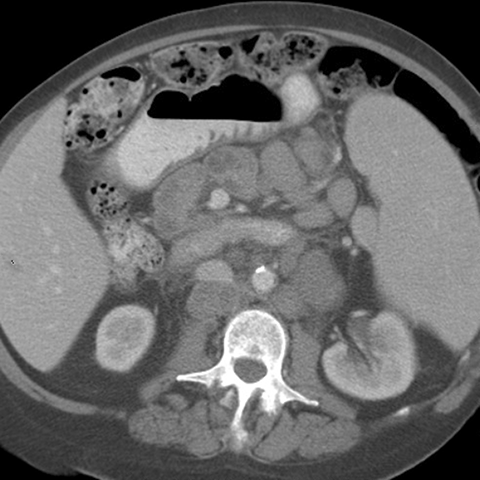

26 year-old male presents with night sweats, weight loss and fever. [3 of 3]